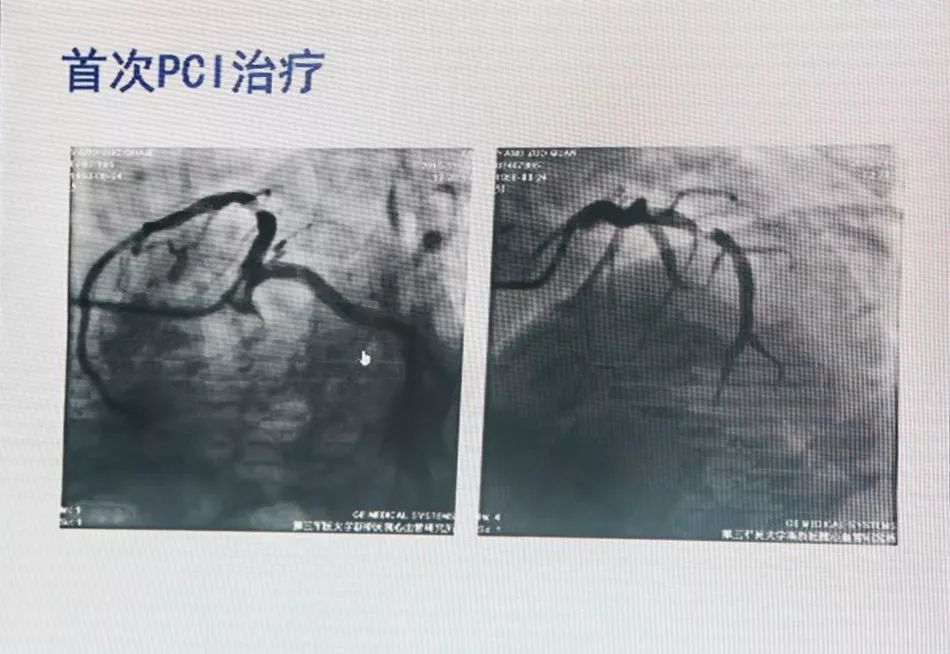

65岁,男性,以“劳力性胸闷胸痛3年,加重11天”入院。

既往糖尿病病史2年,未规律用药;脑梗死病史4年,现遗留步态不稳,未规律用药。

有条件者应尽快进入导管室行急诊冠状动脉造影,以多体位投照明确无夹层及支架膨胀不良。若血管完全闭塞,待球囊扩张部分血流恢复后再行造影。应尽快使导丝通过血栓病变,建议应用软头导引导丝。

支架内血栓形成可能与支架未充分贴壁有关。可用短于支架长度的高压球囊再次PTCA。若造影确认血栓形成可能与支架近或远端内膜撕裂、支架未完全覆盖病变有关,可再次置入支架,观察20 min后,若患者胸痛缓解、血压及心电监测稳定、TIMI血流III级,可视为成功。但应关注,除非有证据显示血栓形成与上述因素相关,否则不可再次置入新支架。Dutch研究发现,首次出现支架血栓的患者,再次置入新支架,发生支架血栓的风险比未置入新支架的患者增加4.2倍。